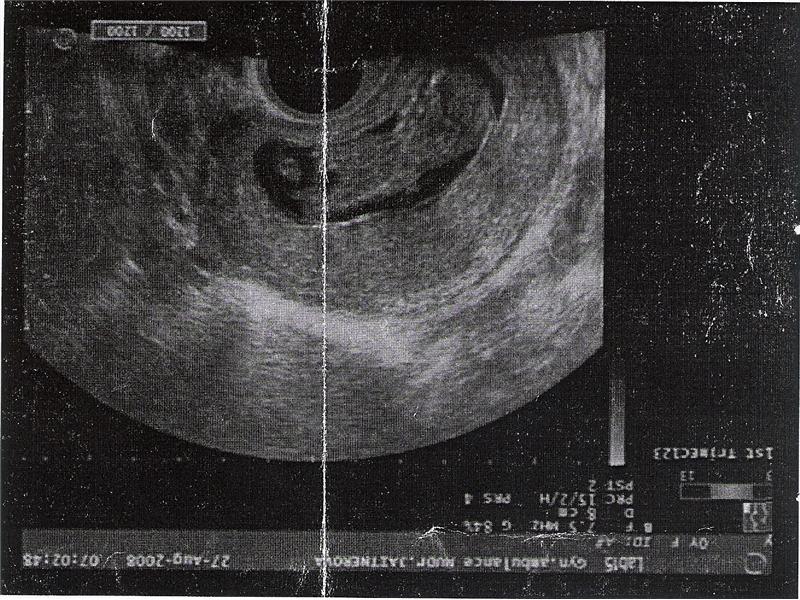

Náš Milda jr.

postupný vývoj našeho broučka